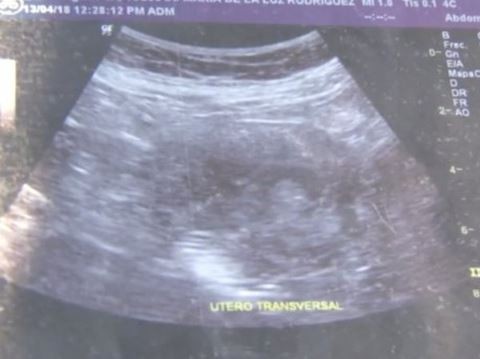

"Các bác sĩ bảo tôi đó là con gái. Các anh nhìn xem, khuôn mặt nhỏ bé này", cụ Maria đưa ra hình chụp siêu âm có bào thai trong đó và chỉ cho phóng viên xem.

Hình ảnh siêu âm đứa bé trong bụng bà Maria de la Luz |